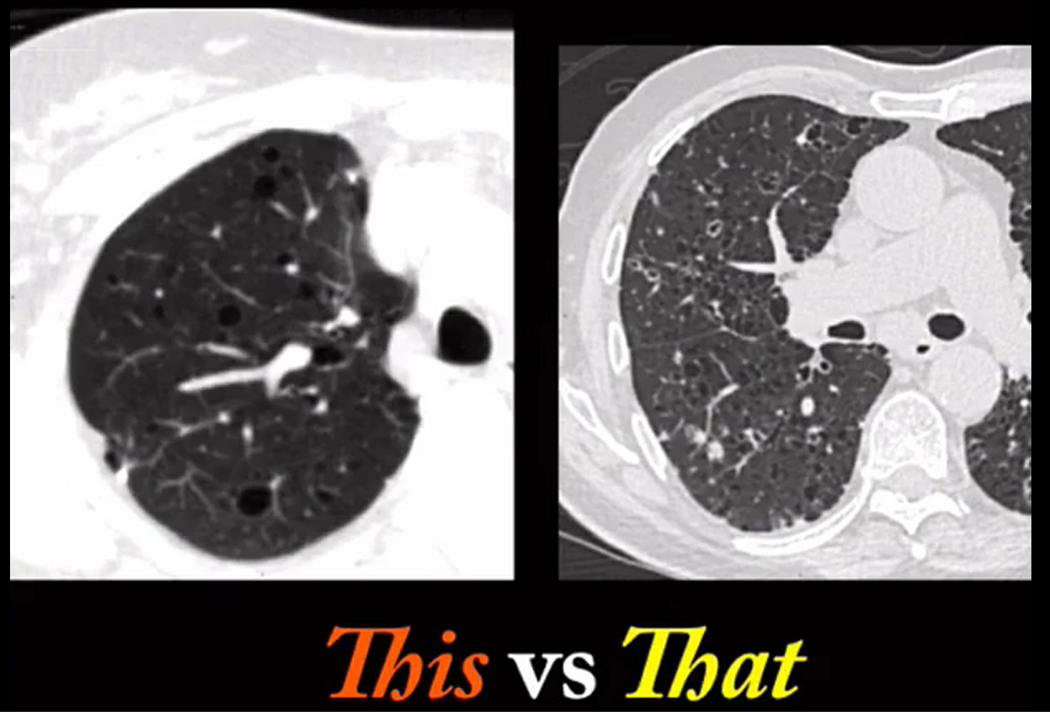

expiratory HRCT images

Diffuse idiopathic neuroendocrine cell hyperplasia (DIPNECH)

multiple small pulmonary nodules and mosaic attenuating from air trapping due to constrictive bronchiolitis

bronchiolar inflammation

Ritalin lung can look like this too